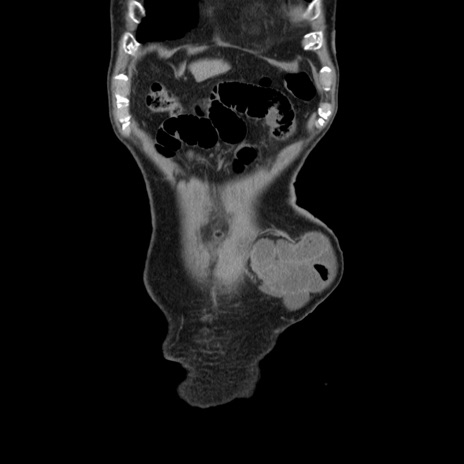

矢状断像

【症例】80歳代男性

【主訴】左側腹部痛、嘔吐

【既往歴】直腸癌(Mile手術)、胆摘

【身体所見】意識清明、BT 35.9℃、BP 221/93mmHg、SpO2 97%(RA) 、腹部:左ストーマ周囲に限局性の腹部膨隆あり。 膨隆部自発痛・圧痛あり・軟。